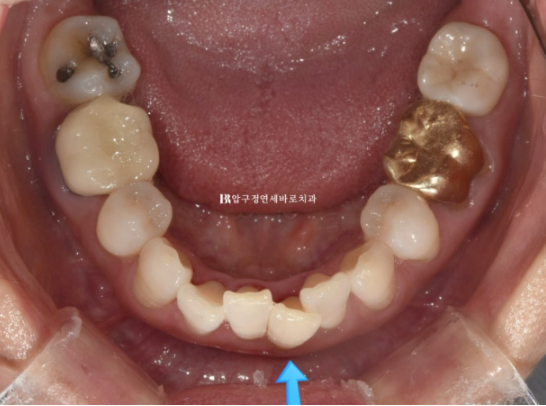

위 앞니 블랙트라이앵글은 치간삭제를 통해 줄었으나 삐뚤했던 아래 앞니가 가지런해지면서 블랙트라이앵글이 생겼습니다. 아래도 마찬가지로 치간삭제를 통해 블랙트라이앵글 사이즈를 줄였지만 치간삭제는 치아에 무리가지 않는 선에서 하는 것이 좋습니다.

24.05

배열에서 가장 많이 벗어난 덕분에 잇몸이 유독 내려갔던 치아를 자세히 보겠습니다.

23.07~24.05

잇몸 퇴축이 회복이 되어 치아뿌리 노출이 줄었습니다.